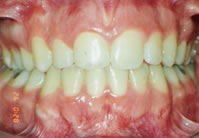

Antes

DepoisTratamento executado sem extrações. Tempo de tratamento de 20 meses. Em nossa clínica abolimos o uso do extra-bucal. Com técnicas mais recentes, temos conseguido resultados melhores e em menos tempo.